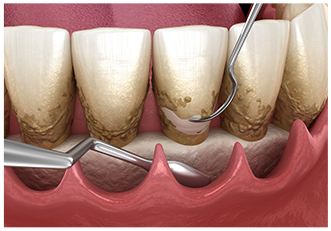

スケーラーという器具を使用し、歯面に沈着したプラークや歯石などを除去します。

特殊な器具を使用してスケーリングでは取り除けない歯周ポケット内部や歯根に付着している歯垢や歯石の除去を行います。